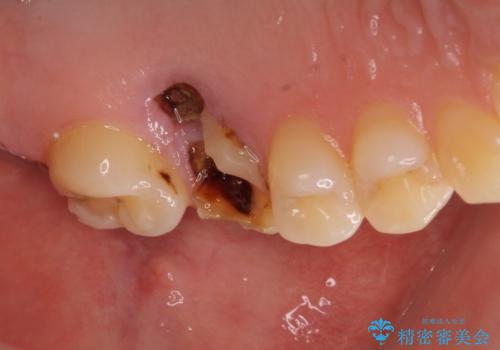

- 抜歯が必要と診断された奥歯を気にして来院された患者様です。

抜歯の上インプラントによる補綴治療を行うこととなりましたが、前歯の叢生も気になるとのことで並行して矯正治療を行うこととしました。

歯列不正は軽微であったので、インビザラインによる矯正治療とし、矯正治療中にインプラント埋入を行う予定としました。

痛みがないので、ボロボロのまま放置していましたが、抜歯後は汚れが溜まりにくくなりスッキリとしたようです。